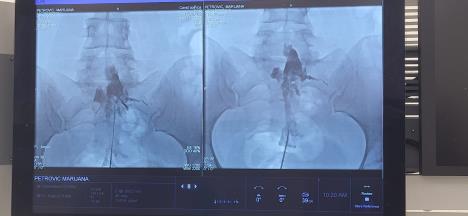

Postupak se izvodi uvođenjem specijalnog katetera (Racz kateter) u epiduralni prostor, najčešće u lumbosakralnom regionu, uz rendgensku (fluoroskopsku) kontrolu.

Postupak se izvodi uvođenjem specijalnog katetera (Racz kateter) u epiduralni prostor, najčešće u lumbosakralnom regionu, uz rendgensku (fluoroskopsku) kontrolu Foto: UKC Vojvodine